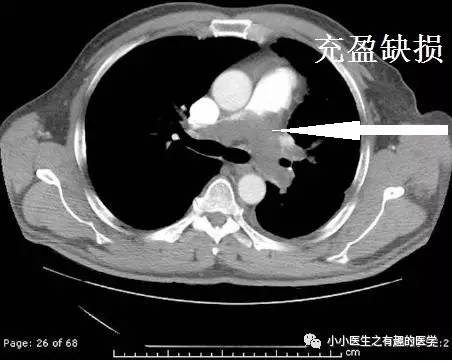

这是什么?妥妥的肺栓塞啊,还能有啥?

是的,这不是肺栓塞,这是肺动脉内膜肉瘤。这不是扯蛋肺栓塞,这是扯蛋肺动脉肿瘤。扯蛋是肯定的,然而,血栓且不肯定。

仔细看看,不对。

充盈缺损的地方,密度不均匀,并且,有强化,血栓里面没有血管,一般不会强化,所以,有可能是肿瘤。